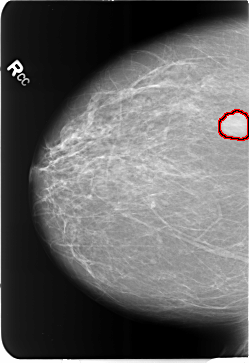

FILE: B_3484_1.RIGHT_CC.OVERLAY

TOTAL_ABNORMALITIES 1

ABNORMALITY 1

LESION_TYPE MASS SHAPE LOBULATED MARGINS CIRCUMSCRIBED

ASSESSMENT 4

SUBTLETY 5

PATHOLOGY BENIGN

TOTAL_OUTLINES 1

BOUNDARY